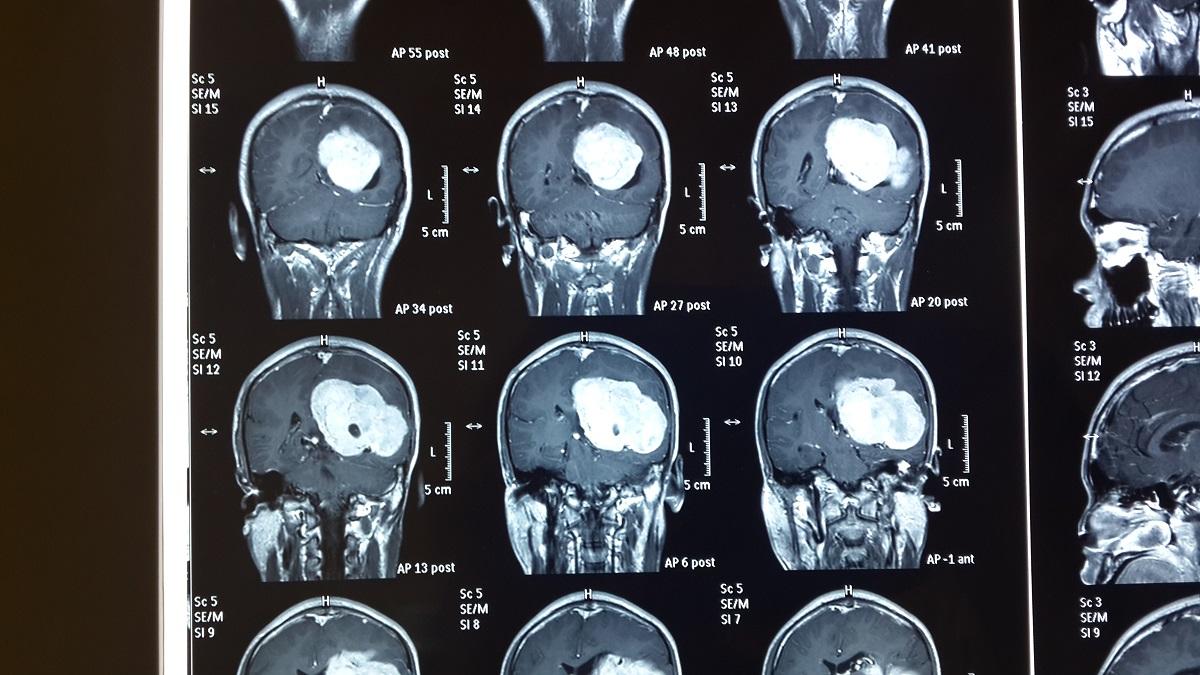

對於腦室內的腦膜瘤,磁力共振和電腦掃描都可以看到其清晰的界線,一般呈橢圓形或不規則狀,當中超過一半腫瘤的內部會有鈣化現象。治療方面則以顯微鏡手術為主,位於側腦室的腦膜瘤通常採用頂枕入路的方式,直接進入側腦室的三角區切除腫瘤。